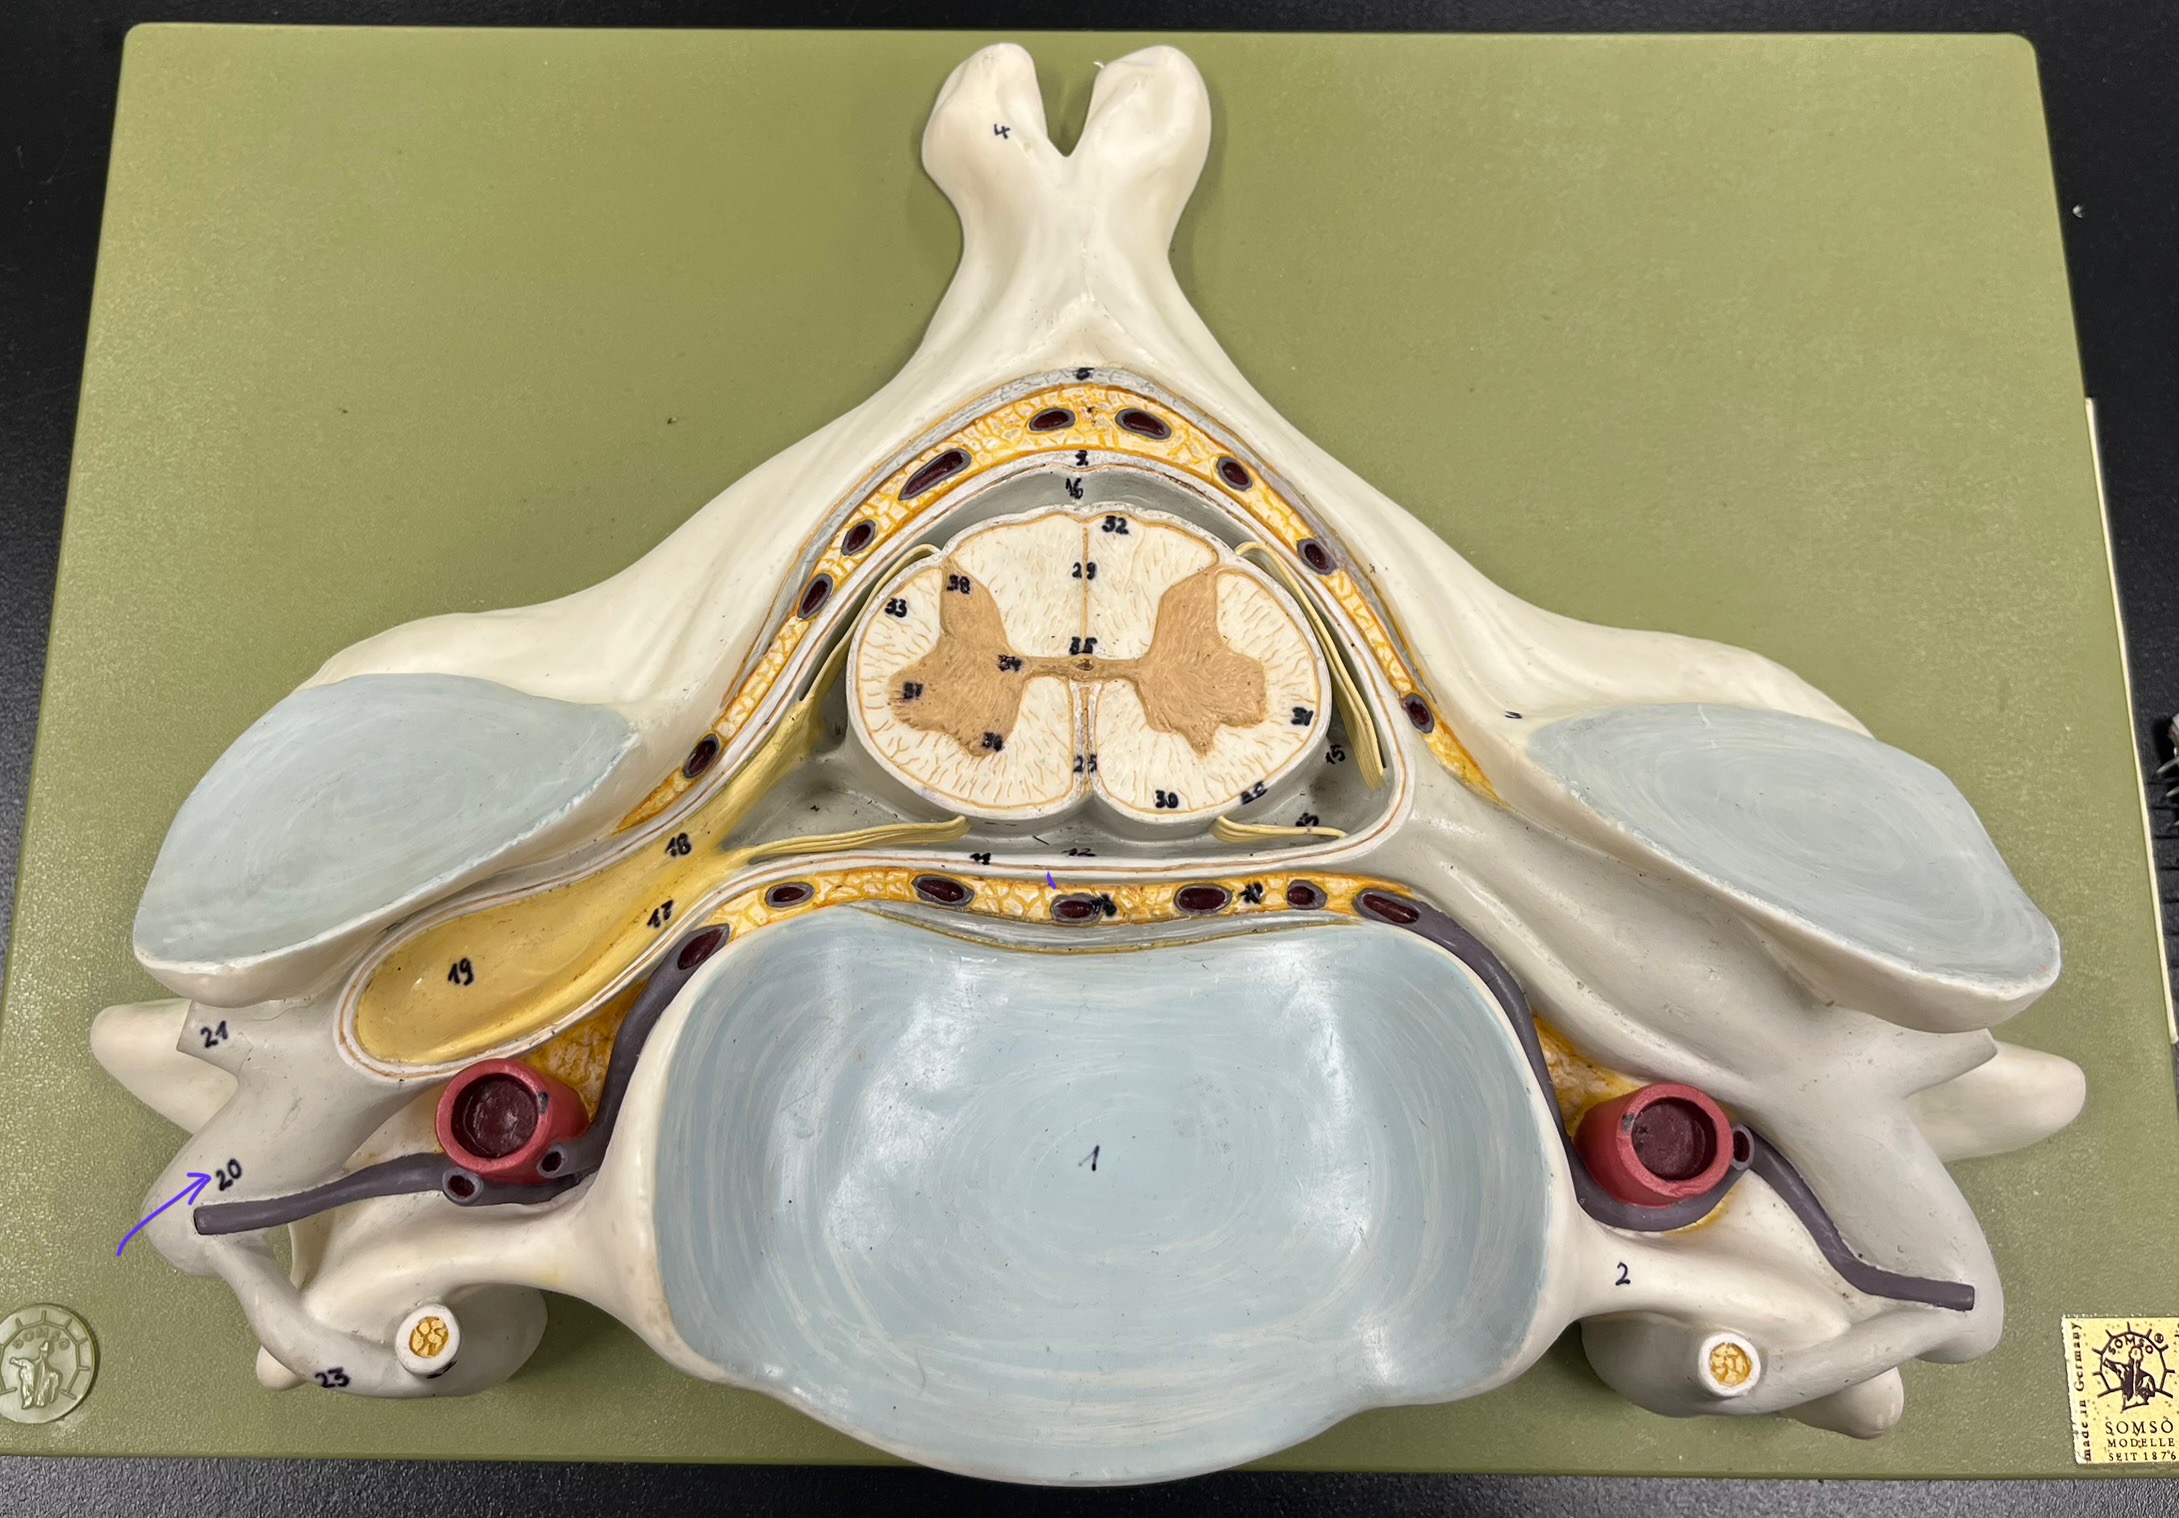

epidural space

dura mater

subdural space

arachnoid mater

subarachnoid space

pia mater

denticulate ligaments

What is the groove here?

anterior median fissure

posterior median sulcus

posterior (dorsal) horn

posterior (dorsal) horn; R—>L

anterior (ventral) horn

lateral horn (selected models)

gray commissure

central canal

anterior column

lateral column

posterior column

white commissure

posterior (dorsal) root ganglion

What is the bulb here?

posterior (dorsal) root ganglion

posterior (dorsal) root

posterior (dorsal) root

anterior (ventral) root

anterior (ventral) root

dorsal ramus

dorsal ramus

ventral ramus

ventral ramus

rami communicantes

rami communicantes

sympathetic chain ganglia

sympathetic chain ganglia